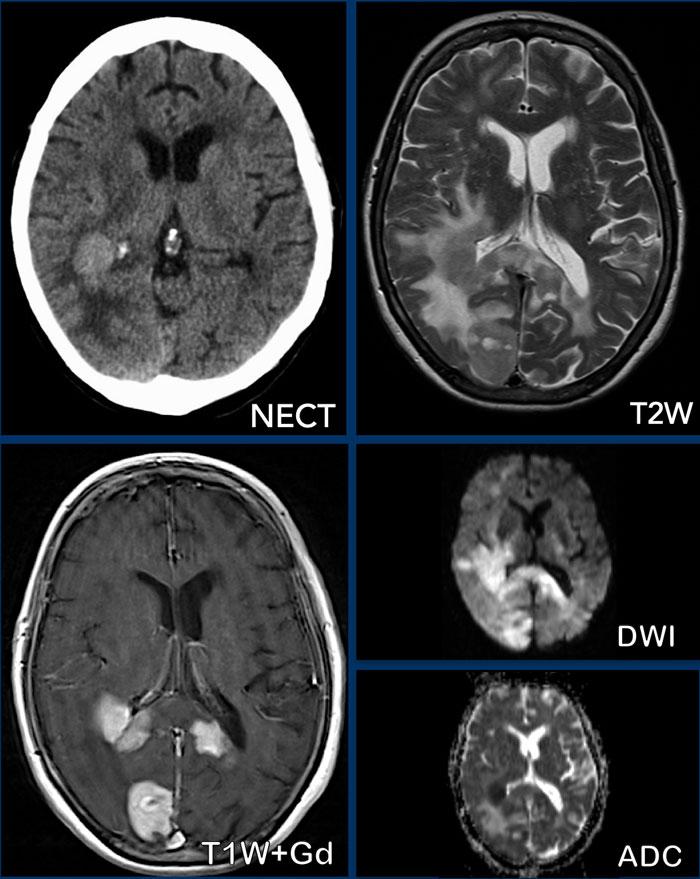

U lympho

Các hình ảnh này của một phụ nữ 76 tuổi, có biểu hiện lú lẫn sau khi ngã.

Hãy quan sát các hình ảnh trước rồi mới tiếp tục đọc.

Câu hỏi:

- Chẩn đoán có khả năng nhất là gì?

- Những dấu hiệu nào điển hình cho chẩn đoán này?

Các dấu hiệu bao gồm:

- Tổn thương tăng tỷ trọng trên CT không tiêm thuốc cản quang kèm phù não do mạch máu.

- MRI cho thấy nhiều tổn thương ngấm thuốc dạng đặc và hạn chế khuếch tán.

- Trên chuỗi xung T2W, các tổn thương biểu hiện giảm tín hiệu.

- Một tổn thương nằm ở thể chai và một tổn thương khác nằm cạnh não thất.

Tất cả các dấu hiệu này đều điển hình cho u lympho nguyên phát hệ thần kinh trung ương, khác với u lympho hệ thống.

Các khối u này chiếm 6-7% tổng số u hệ thần kinh trung ương và mô học là u lympho tế bào B không Hodgkin.

Chúng thường nằm ở vùng cạnh não thất dưới màng nội tủy, thể chai và hạch nền.

Luôn nghĩ đến u lympho khi gặp tổn thương ngấm thuốc dạng đặc nằm gần não thất.

Hình ảnh tăng tỷ trọng trên CT, giảm tín hiệu nhẹ trên chuỗi xung T2W cũng như hạn chế khuếch tán được giải thích là do mật độ tế bào dày đặc của mô u lympho.

Ở bệnh nhân suy giảm miễn dịch, kiểu ngấm thuốc có thể là dạng vòng nhẫn.

Bệnh nhân này có nhiều phù não, nhưng trong nhiều trường hợp phù não rất hạn chế.